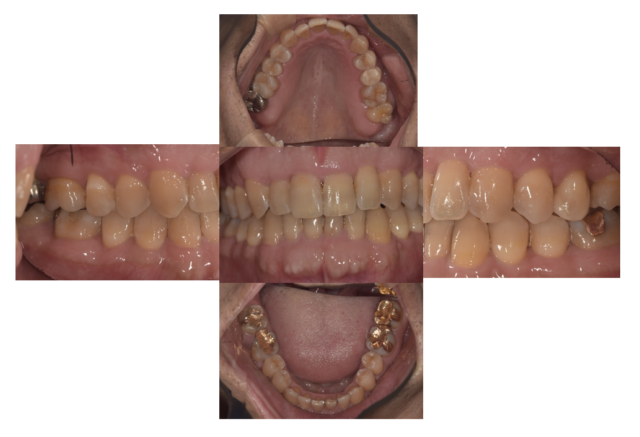

主訴:歯並びが悪く抜けて見える

After

通院時の年齢 | 55歳 |

---|---|

性別 | 男性 |

通院回数 | 20回程度 期間1年半 |

通院目的 | ワイヤー矯正では歯が痛くなりインビザラインを用いた痛くない矯正をしたい |

処置内容 | インビザライン |

費用 | 費用80万(月々管理費用5500円) |

デメリット・注意点 | 移動がスムーズに行われない場合は追加でねじを埋入して移動を促す場合がある 多少なりとも歯が動く際は痛みがある 20時間以上の装着時間が必要 |

備考 | 歯並びは見た目だけでなく咬むことの健康とご自身の歯を長持ちさせることに役立ちます |